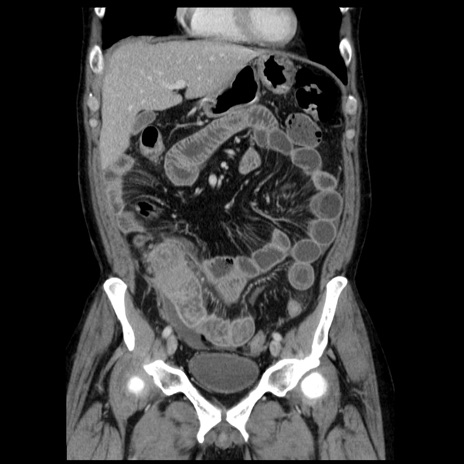

横断像

【症例】40歳代男性

【現病歴】2日前から胃痛あり。徐々に周期的な激痛に変化した。本日になっても激痛があるため受診。

【身体所見】意識清明、BT 38-39℃台あり、腹部:膨満、やや硬、右下腹部に圧痛あり。

【データ】WBC 8500、CRP 23.26